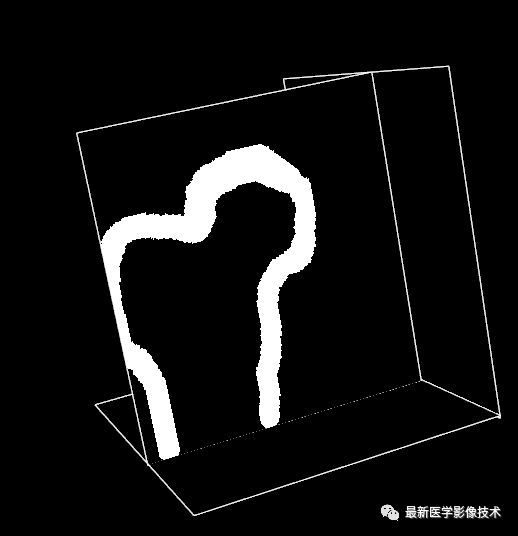

然后在该层中再绘制出背景大致区域Mask并设置成255,其它区域为0,如图所示。